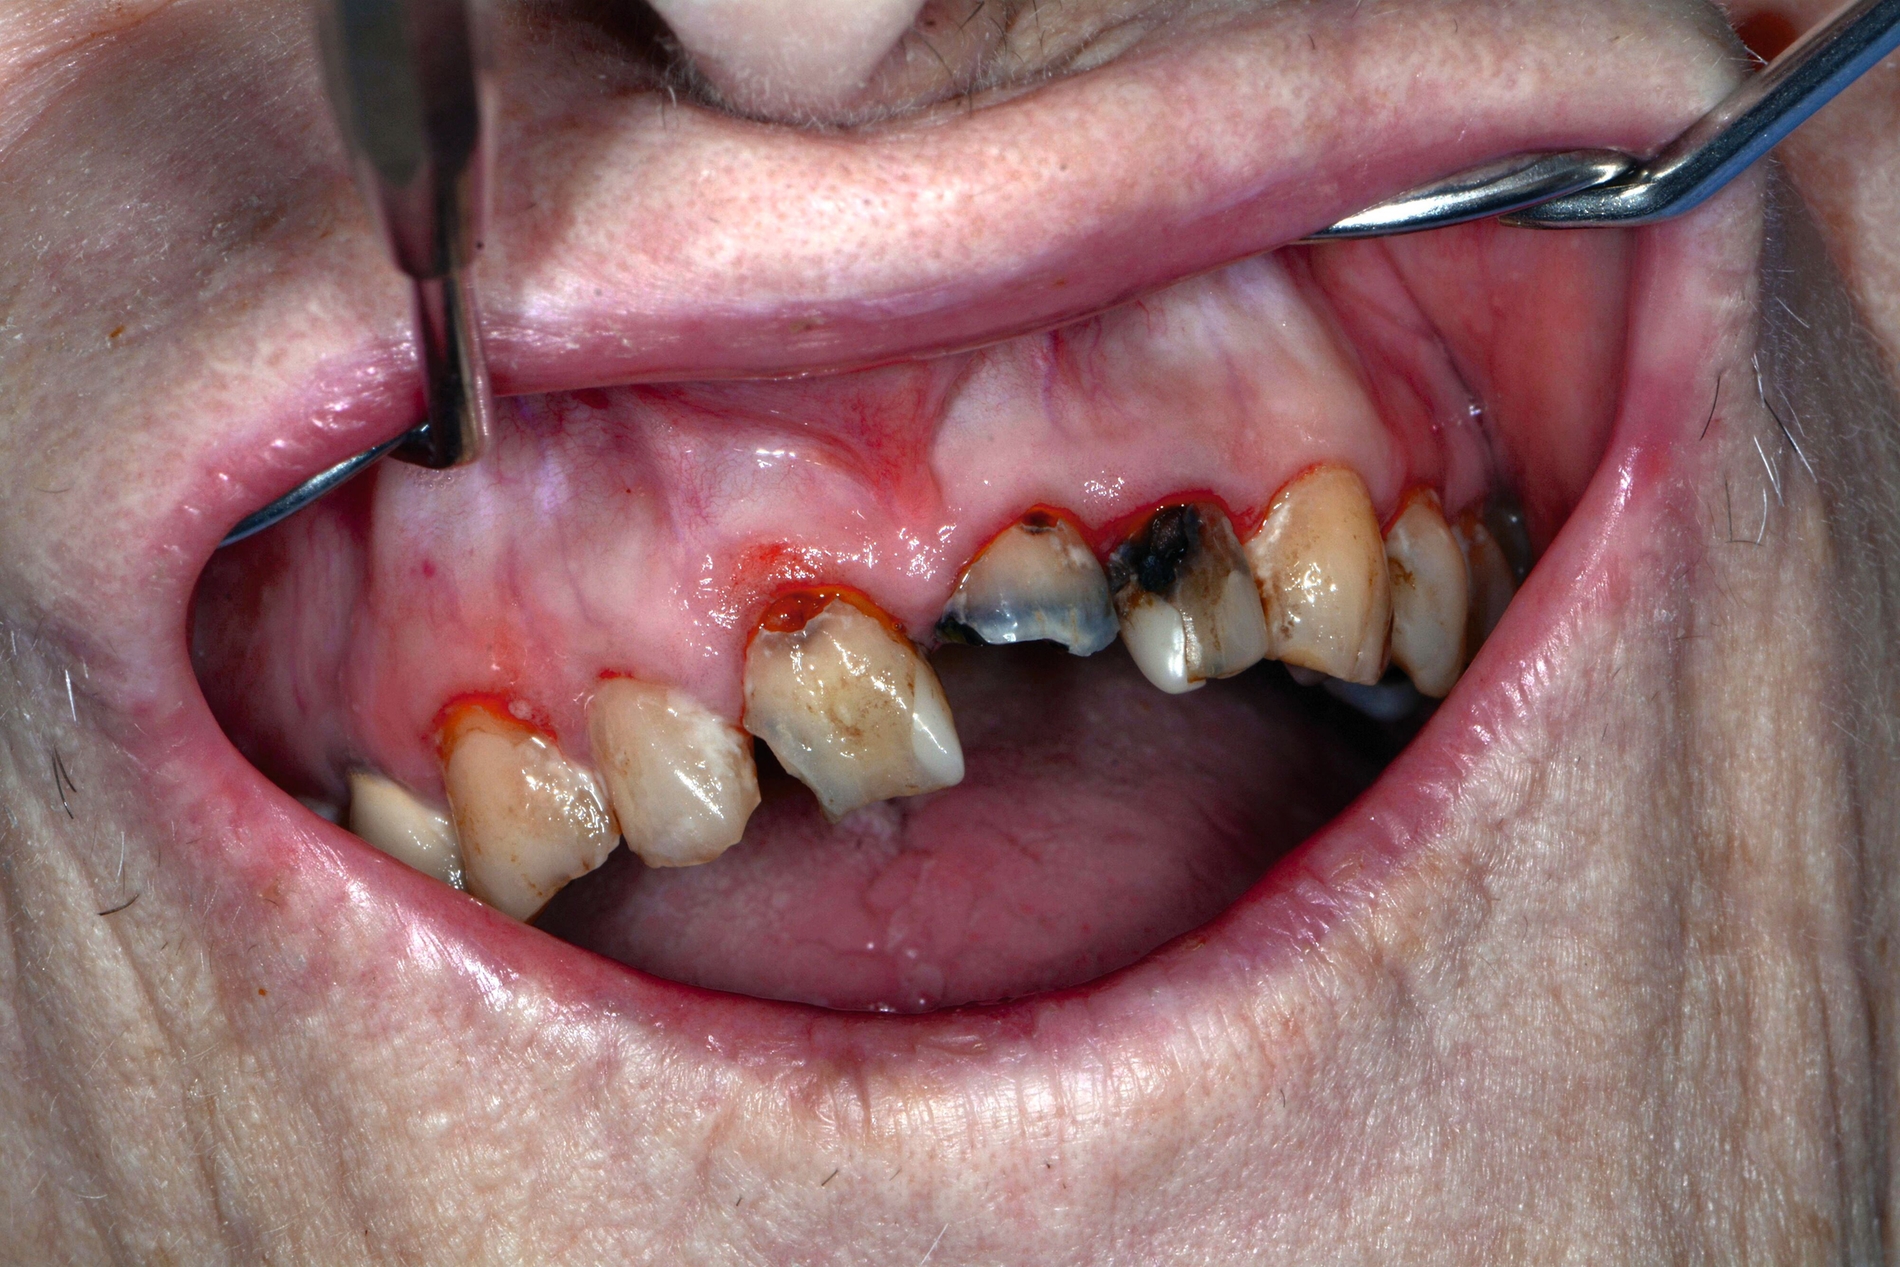

Die Herausforderungen der zahnmedizinischen Betreuung im höheren Lebensalter liegen außerhalb der Mundhöhle und haben nur indirekt etwas mit dem Alter zu tun. Im höheren Lebensalter steigt die Gefahr für Erkrankungen und Funktionseinschränkungen wie Gebrechlichkeit (Frailty), Demenz und Depressionen und/oder internistische sowie muskuloskelettale Erkrankungen. Diese Erkrankungen und Funktionseinschränkungen führen zu einer reduzierten Mundhygienefähigkeit der betroffenen Person. In der Folge kommt es besonders im vorgeschädigten Gebiss zu einer schnellen Progression kariöser oder parodontaler Erkrankungen. In Kombination mit organischen Funktionseinschränkungen wie zum Beispiel einer medikamenteninduzierten Xerostomie führt die Summation der Noxen – auch bei Personen, die ihre Mundgesundheit bis dato aufrechterhalten haben – zu oralen Komplikationen wie Zahnverlust und Entzündungen (Abbildung 1).